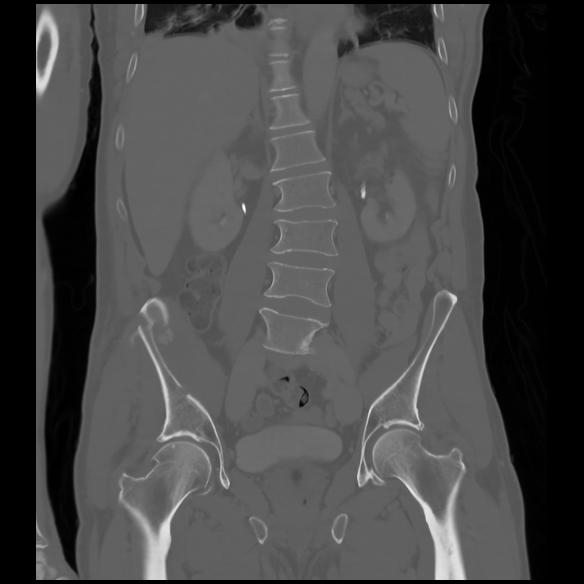

6 CUERPO,CE,Coronal,3.000,CUERPO,Coronal,